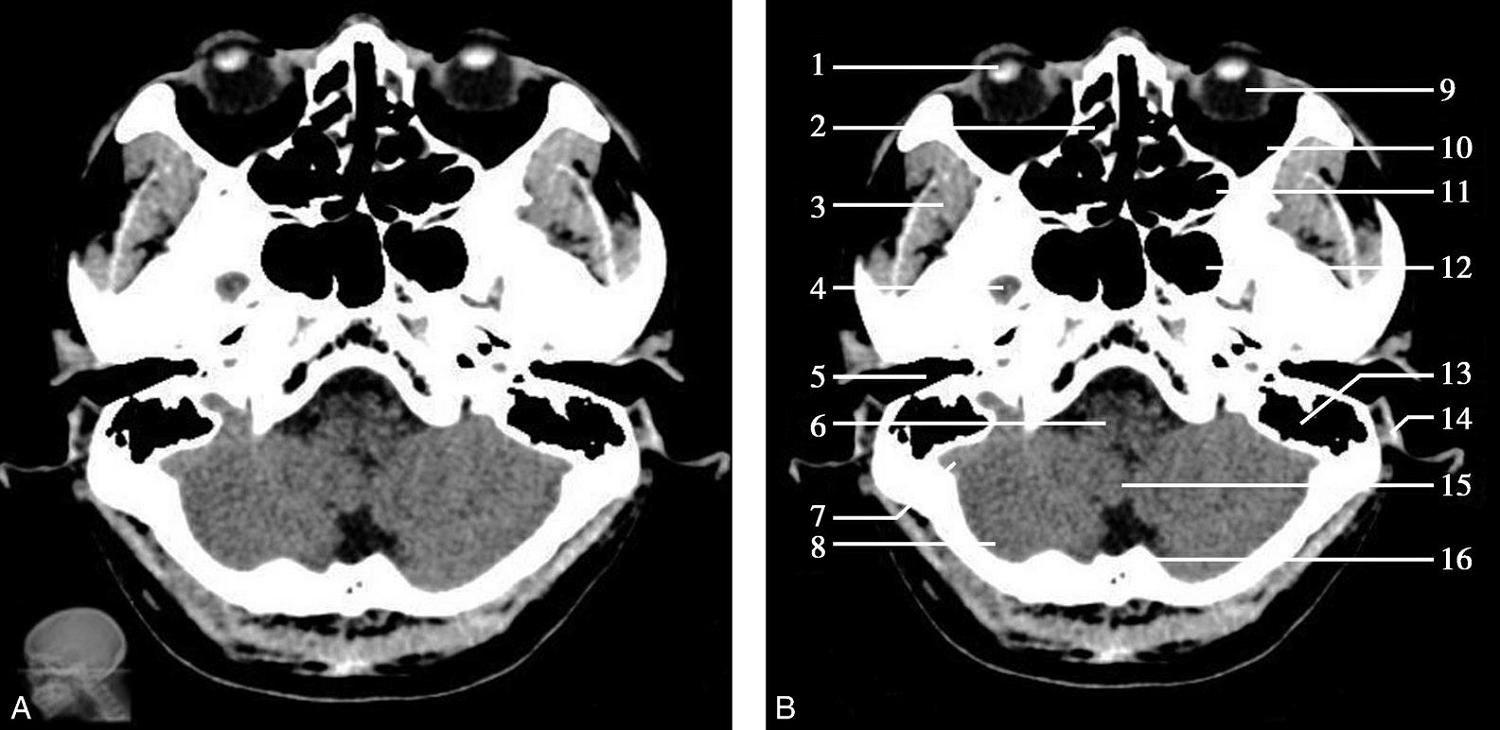

重要结构:卵圆孔、棘孔、破裂孔、斜坡、颞骨岩部、颈静脉孔(图1-2-1、图1-2-2)。

图1-2-1 颅底层面

A.横断面;B.横断面标注

1.晶状体;2.筛窦;3.颞肌;4.中颅窝底;5.外耳道;6.延髓;7.乙状窦;8.小脑半球;9.眼球;10.眼眶;11.上颌窦;12.蝶窦;13.乳突;14.耳郭;15.小脑蚓部;16.枕内隆凸

层面前部呈开口向前的“V”字形,正中为鼻中隔,向两侧依次为筛窦和眼眶,眼眶内前部为眼球,后部为眶脂体。翼腭窝位于眼眶后部,窝内含有脂肪并有上颌神经通过。层面中部为蝶骨体,蝶骨体中部可见含气蝶窦,蝶窦后方为枕骨基底部,两者呈前后关系,其上面构成斜坡。蝶窦两侧为蝶骨大翼,其后外侧缘处由前向后可见卵圆孔和棘孔,分别有下颌神经和脑膜中动脉通过。斜坡外侧、岩骨尖前方为破裂孔。蝶骨大翼与眶外侧壁的颧骨借颧弓相连,颧弓和蝶骨大翼之间有咬肌及颞肌。层面中部外侧为外耳道。颞骨岩部呈“八”字形,相互之间借破裂孔软骨、蝶岩软骨结合和岩枕软骨结合连接。岩部后外侧的乳突部内可见乳突小房,乳突部与枕骨相接。岩骨后部可见颈静脉孔,内有颈内静脉、舌咽神经、迷走神经和副神经通过。层面后部为颅后窝,其内可见延髓,延髓前方为延髓前池,内有椎动脉,后外侧为小脑半球下部,后方为第四脑室、小脑扁桃体及小脑蚓部。